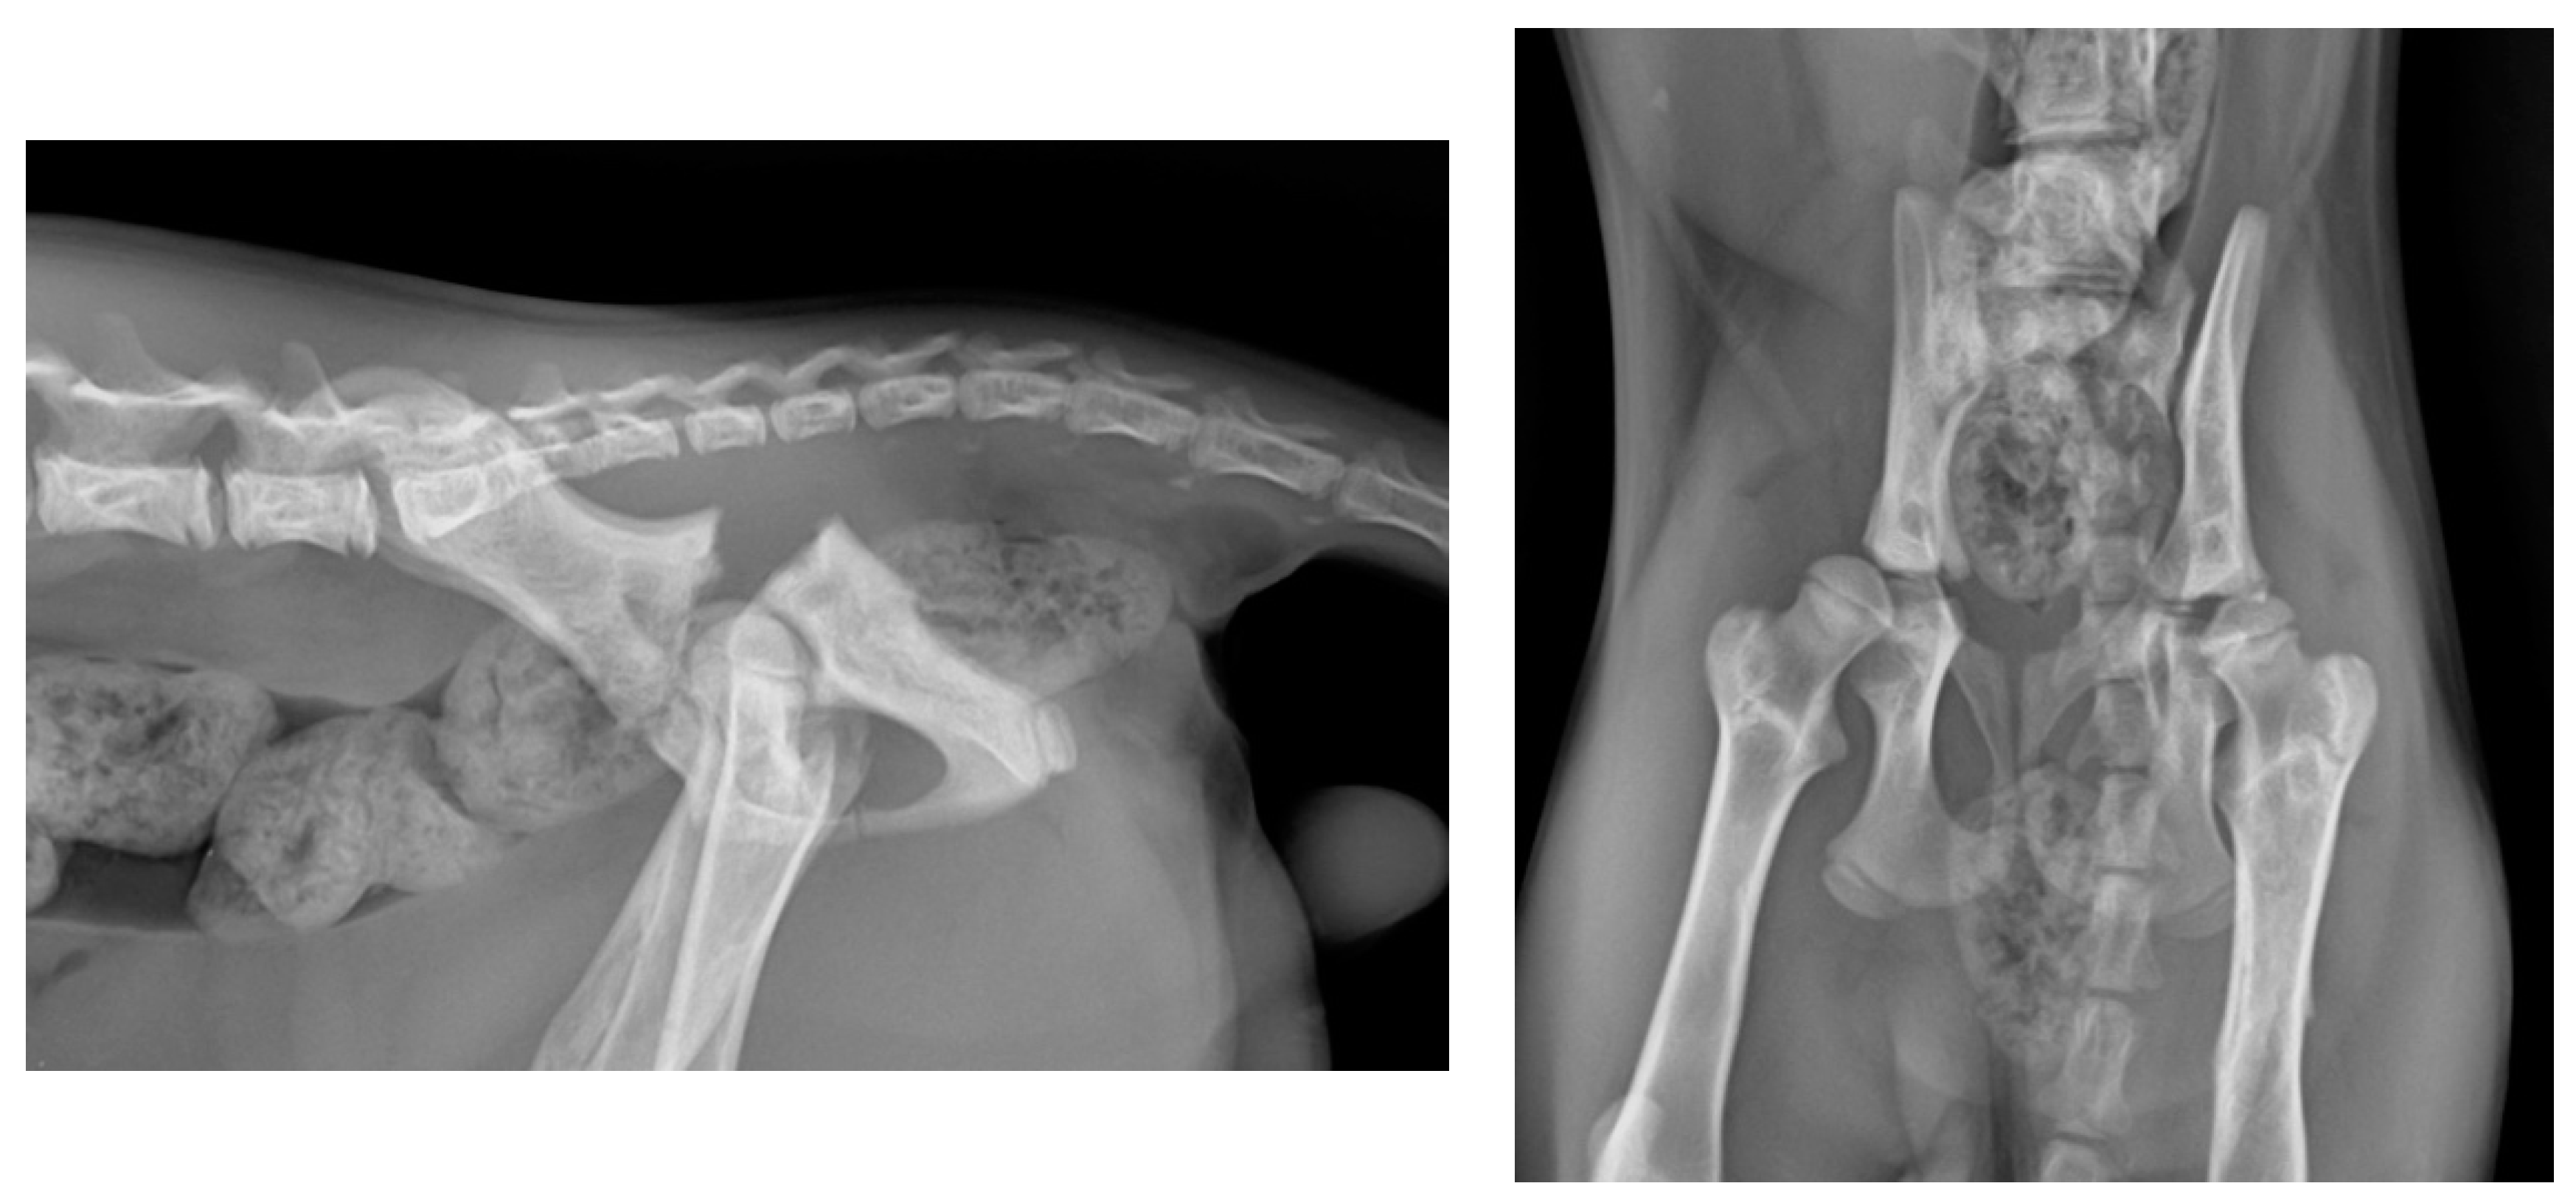

3. Results

4. Discussion